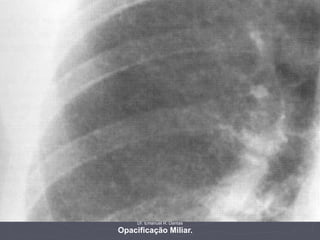

Opacificações miliares.

Este filme pertence a um

homem de 32 anos com

imunodeficiência. Ele mostra

a típica opacificação miliar

característica de TB.

Dr. Emanuel R. Dantas

Opacificação Miliar.